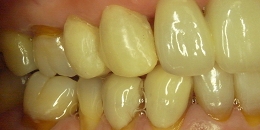

セラミックに換えた状態

セラミックの歯に換えました。

見た目もキレイですが、金属アレルギーの軽減や口臭治療にもなります。